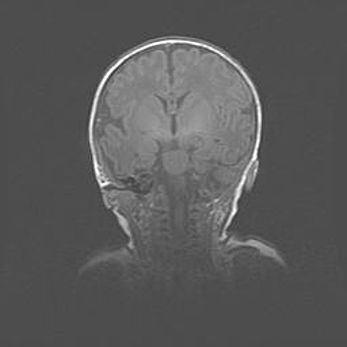

Открытая гидроцефалия.

Возраст: 9 месяцев 12 дней

Вес: 6800 г

Пол: мужской

Окружность головы: 41,5 см

Срок гестации: 28 недель

Гидроцефалия головного мозга у новорожденных имеет характерный признак: опережающий рост окружности головы приводит к визуально хорошо определяемой гидроцефальной форме сильно увеличенного в объёме черепа. Детские неврологи определяют следующие симптомы гидроцефалии у грудничков: выбухающий напряжённый родничок, частое запрокидывание головы, смещение глазных яблок к низу.